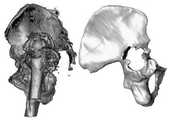

도 18은 부분적인 두개골에 대한 재건 결과 및 재건 오차에 대한 평균 거리 맵이다.

18 is an average distance map for reconstruction results and reconstruction errors for partial skulls.